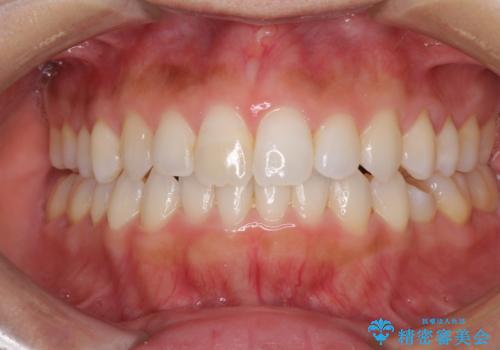

下顎前歯と上顎の部分矯正

- 上下の前歯の叢生を気にして来院された患者様です。

前歯のみの矯正治療を希望でしたが、上顎臼歯が舌側転位していたため、上顎は全体を、下顎は前歯のみを矯正治療することとしました。

矯正治療は上下全顎を行うことが大前提ですが、費用などの点から、今回は部分矯正を選択することとなりました。

患者様本人は咬みにくさを感じていないようですが、部分矯正は咬み合わせの改善が困難であることが多く、咬みにくさが残ることがあります。